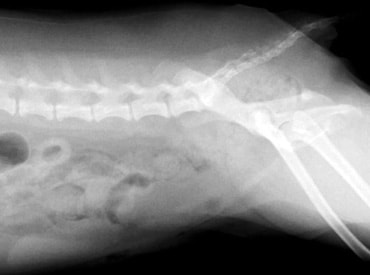

【胃拡張胃捻転を起こしたレントゲン写真】

黒く大きく見えるのがガスで充満した胃です

【整復手術後のレントゲン写真】

拡張した胃や、ガスは見えなくなりました